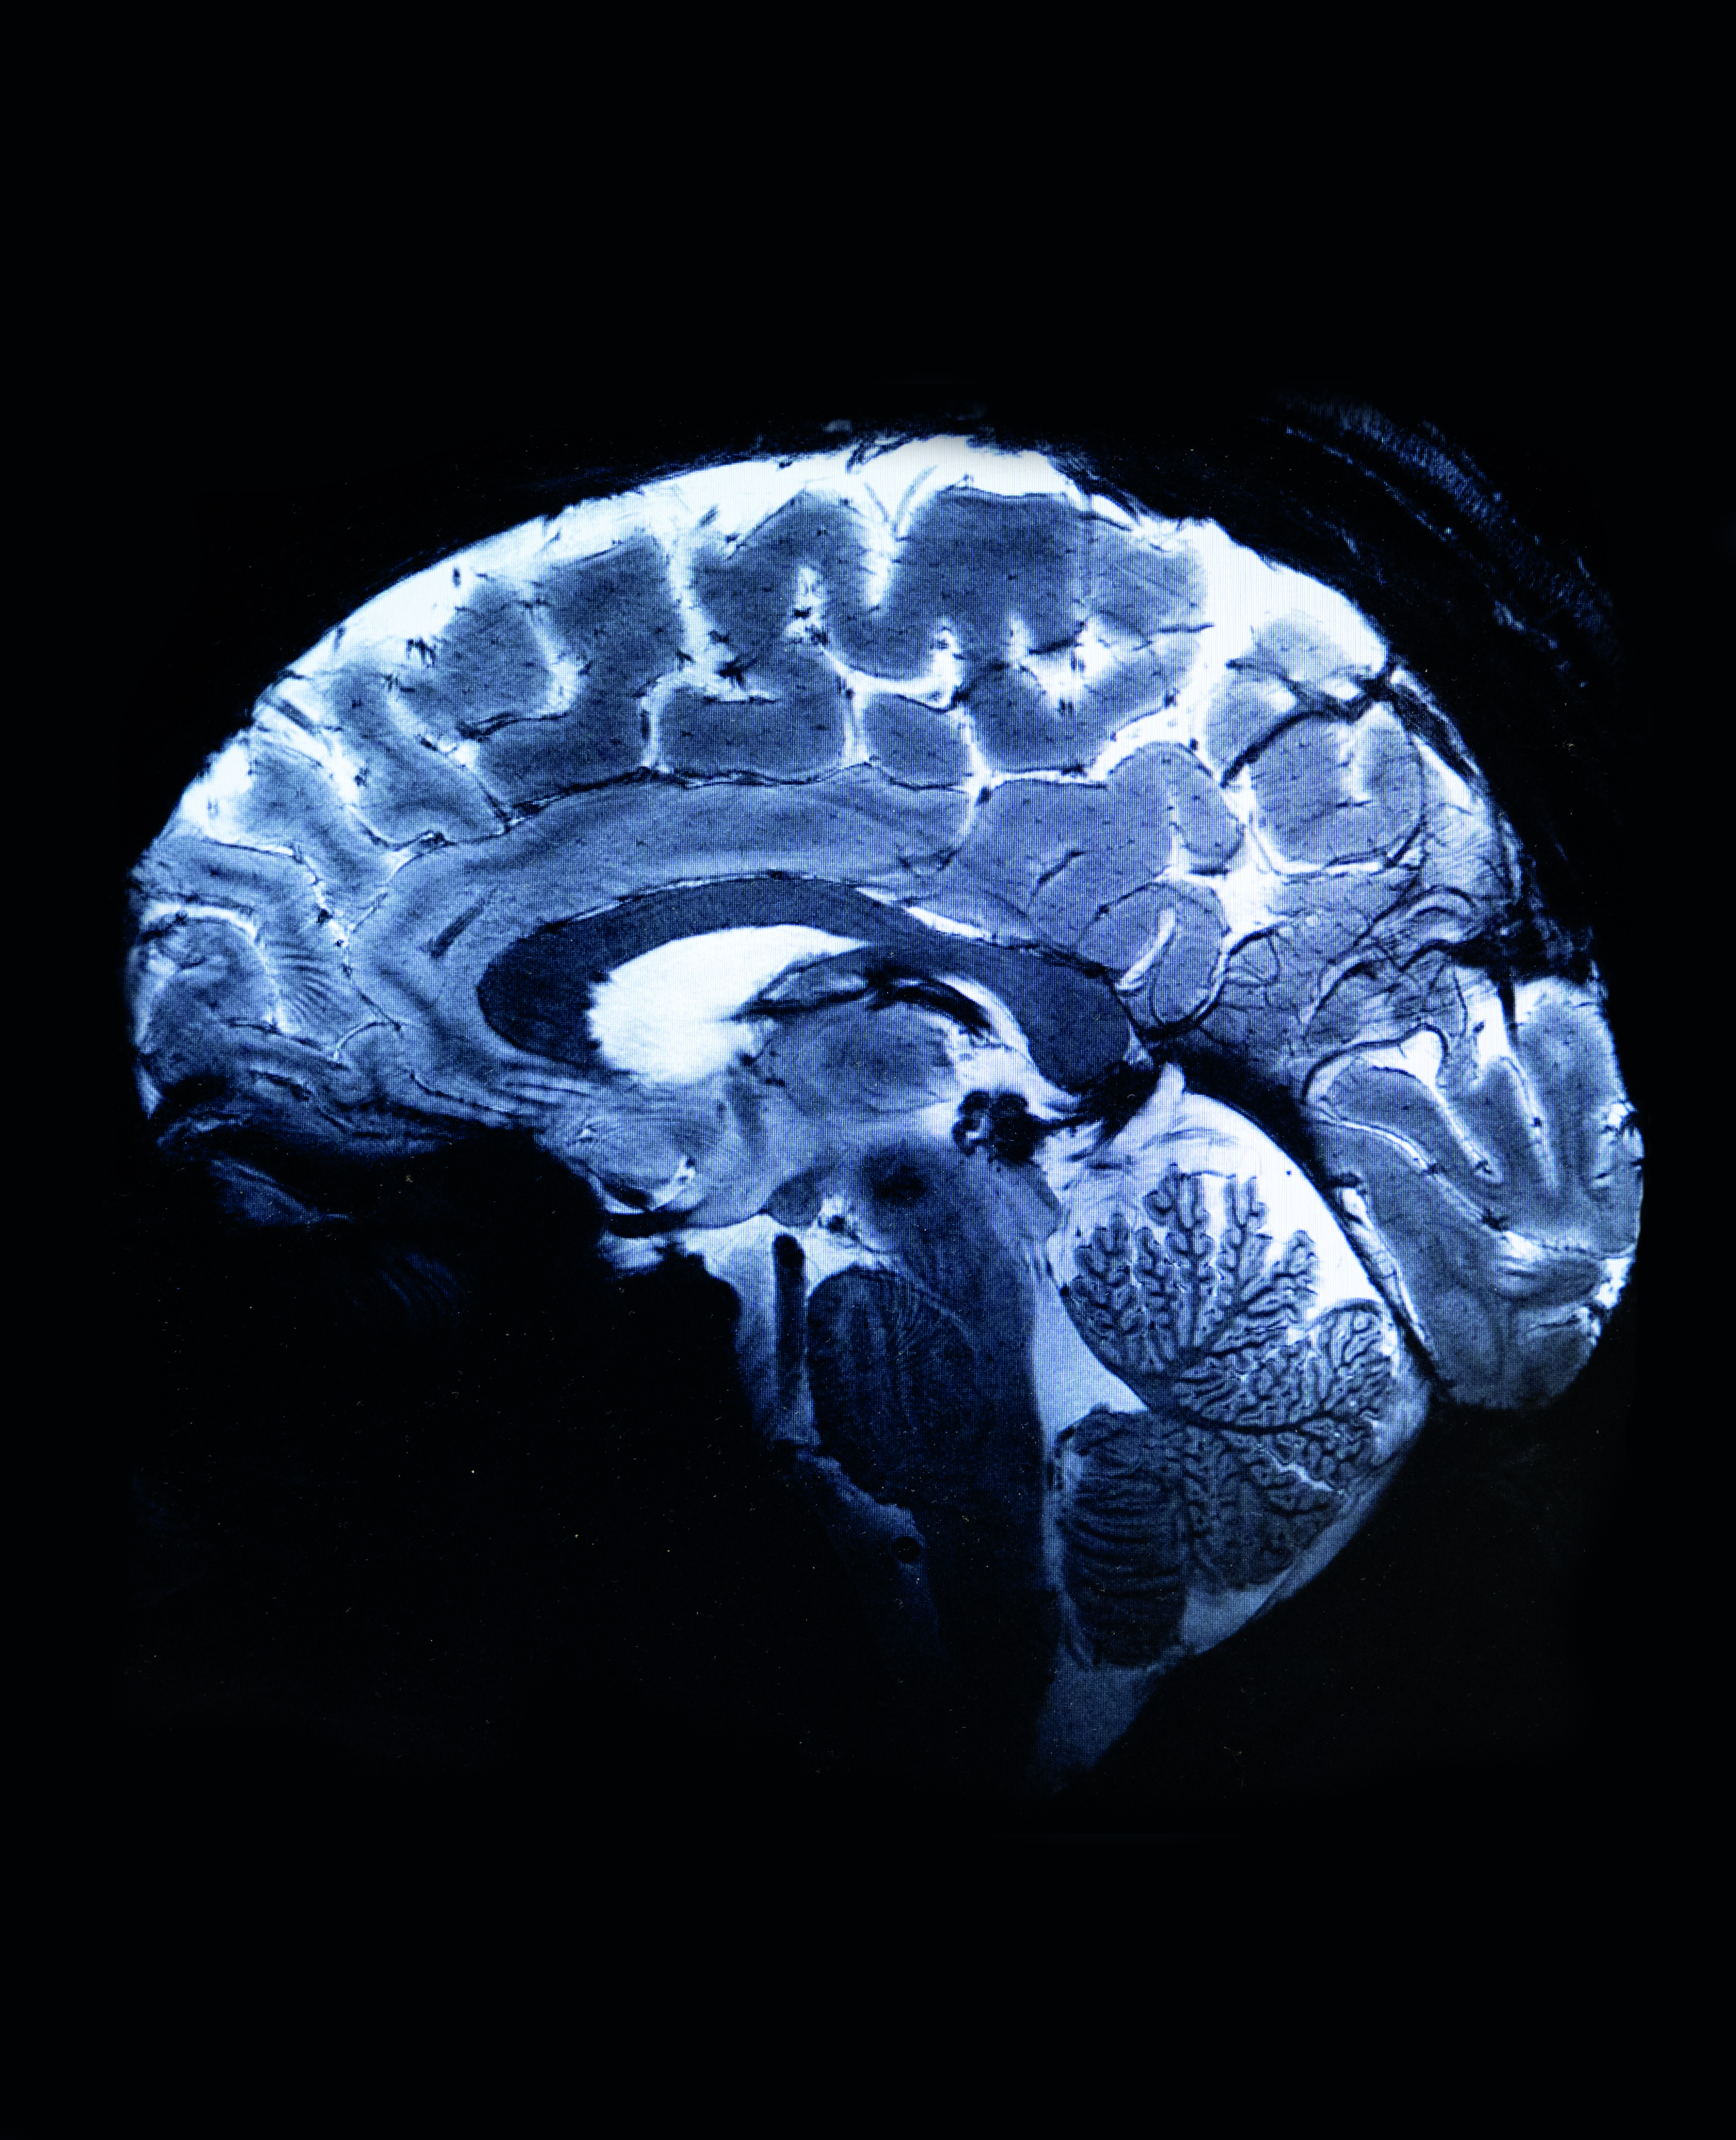

Κεντρική φωτογραφία: Ηλεκτροεγκεφαλογράφημα πραγματοποιείται σε εργαστήριο το οποίο κάνει έρευνα για την αϋπνία, το Πάρκινσον και το Αλτσχάιμερ. Φωτ. © Leah Nash for the Washington Post/Getty Images/Ideal Image